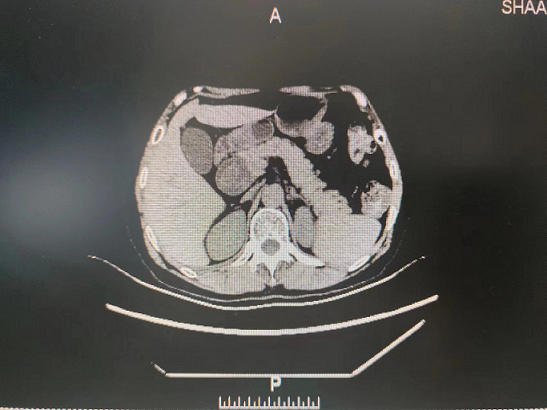

患者5月9日来我院就诊,门诊以“胆总管囊肿”收住院。入院后予完善相关检查后诊断:1.胆总管囊肿(Ⅰ型)并胆总管结石2.胆管炎?。随后给予抗炎、补充电解质,营养风险评估,营养支持等治疗,组织专家进行围术期术前评估、讨论,制定手术计划方案并征得家属和本人同意后,5月15日在普外科田德福主任的带领下,在任斌副主任、杨洲明主治医师的配合下及麻醉科的协助下,对患者行胆总管囊肿切除+胆总管空肠ROU-en-Y吻合术,手术顺利,病理结果提示无癌变。术后在何慢护士长团队的精心护理下,患者第2天就下床活动,第4天进流食。术后没有发生腹腔感染、出血、吻合口漏等相关并发症,术后相关实验室检查结果无异常,5月29日患者痊愈出院。

外科第一党支部书记、普外科主任田德福主任医师表示,胆总管囊肿为先天性胆总管囊状扩张症,发病率低,可以并发结石、有癌变的可能,手术治疗是主要治疗手段。胆总管囊肿切除需要做到胆总管囊肿切除+胆总管空肠ROU-en-Y吻合术,在普外科手术中属难度较高的四级手术,开展这一高难度手术,对普外科医生来说具有很大的挑战性,不但要求具备精湛技术,更需要对患者高度负责的精神。此次手术的成功开展使得医院普通外科在高难度肝胆外科领域得以进一步拓展,同时也增加了科室进一步拓展此项技术的信心。